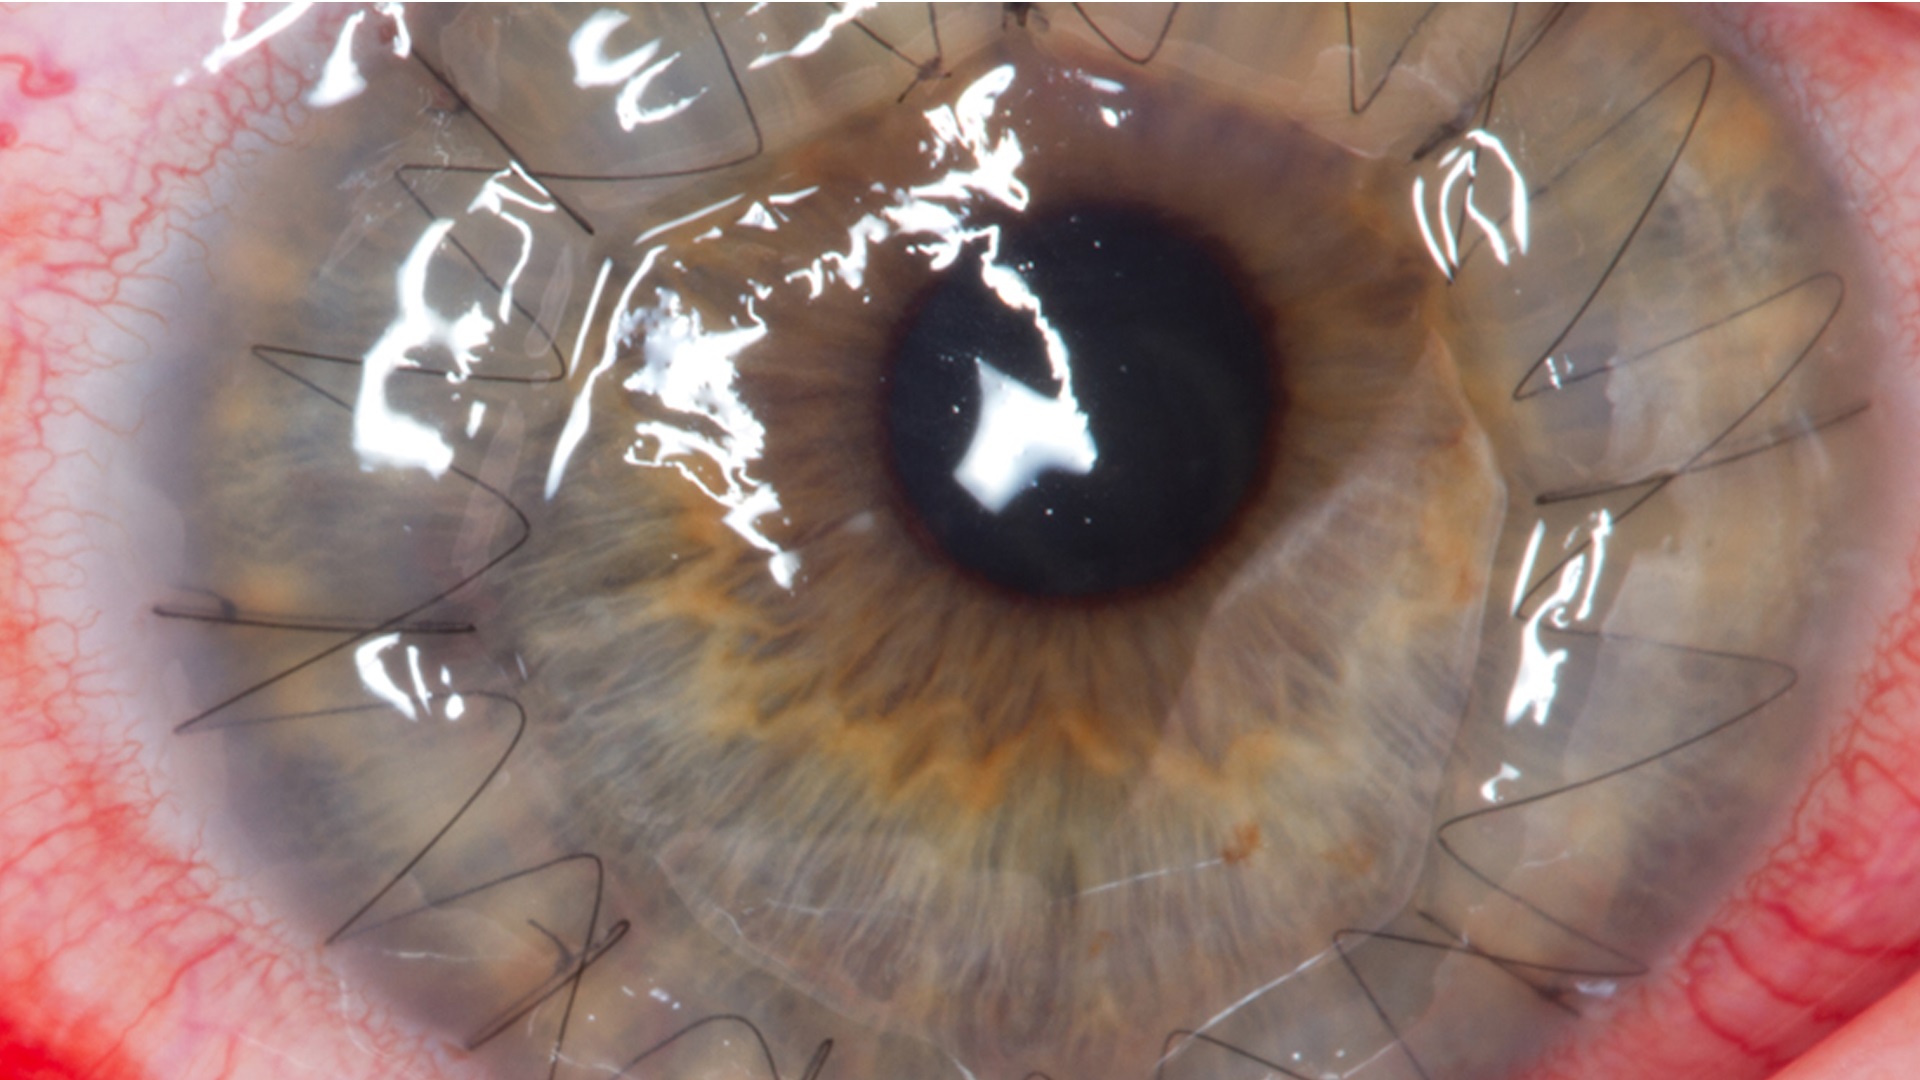

हमीदिया अस्पताल की नेत्र रोग विशेषज्ञ डॉ. अदिति दुबे ने बताया कि उनके पास आए ज़्यादातर मामले कार्बाइड वाले पटाखे के ही हैं जिनमें कॉर्निया इंजरी हुई है। बारूद और कार्बाइड के कण आंख में जाने से आंख का काला मोतिया (Cornea) सफेद पड़ रहा है।

ट्रांसप्लांट: दो बच्चों के लिए एंब्रायोटिक मेम्ब्रेन ट्रांसप्लांट (Embryotic Membrane Transplant) की व्यवस्था की जा रही है। यह जले हुए या गंभीर सूजन वाली आंखों की सतह पर झिल्ली लगाकर इलाज करने की सर्जिकल प्रक्रिया है।